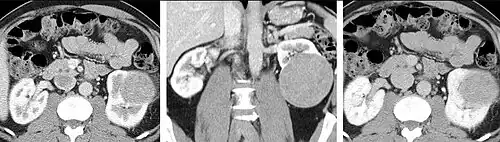

Detection and characterization of renal parenchymal masses is a frequent indication for CT. An initial noncontrast CT is important for detecting calcium or fat in a lesion, and to provide baseline attenuation of any renal masses. Following noncontrast scanning, intravenous contrast is injected and a corticomedullary phase is obtained at approximately 70 seconds (figure 7a, 7b). The corticomedullary phase is characterized by enhancement of the renal cortex as well as the renal vasculature. This phase is valuable in the evaluation of benign renal variants, lymphadenopathy and vasculature, however certain medullary renal masses may not be visible during this phase due to minimal enhancement of the medulla and collecting system. The parenchymal phase is obtained approximately 100–200 seconds after the injection of contrast material (figure 7c). Parenchymal phase imaging demonstrates continued enhancement of the cortex, enhancement of the medulla, and various levels of contrast material in the collecting system. The parenchymal phase is highly important for the detection and characterization of renal masses, parenchymal abnormalities, and the renal collecting system. This method of imaging does not evaluate for abnormalities of the collecting system.

Common renal masses can occasionally be differentiated from each other using this imaging technique. Renal cell carcinomas and oncocytomas typically demonstrate intense heterogeneous enhancement on the parenchymal phase images and cannot be reliably differentiated from each other but can be distinguished from other renal masses. Angiomyolipomas (AML's) also demonstrate intense contrast enhancement but characteristically contain macroscopic fat which can be detected on the noncontrast images, and can help to differentiate AML's from renal cell carcinomas and oncocytomas. Renal lymphoma on the other hand, will often have decreased enhancement when compared to the renal parenchyma on the parenchymal phase images.

- FIGURE 7. Selected images from a renal mass specific protocol CT. Corticomedullary phase (axial 7a) demonstrates peripheral enhancement of the renal cortex with minimal opacification of the renal medulla. There is a large renal cell carcinoma in the left kidney (right in image) which can be differentiated from the normal renal parenchyma by the heterogeneous and differential enhancement. The renal artery and vein are opacified in this phase as well. The collecting system is not opacified (coronal reformat 7b). In the parenchymal phase, the renal cortex and the medulla are enhancing. The renal cell carcinoma in the left kidney is not as well defined when compared to the corticomedullary phase images, but is actually slightly more conspicuous. There is some contrast noted within the collecting system during this phase (7c).